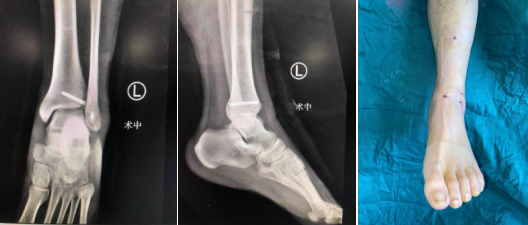

术后X线(左/中图),术后外观:创口很小(右图)